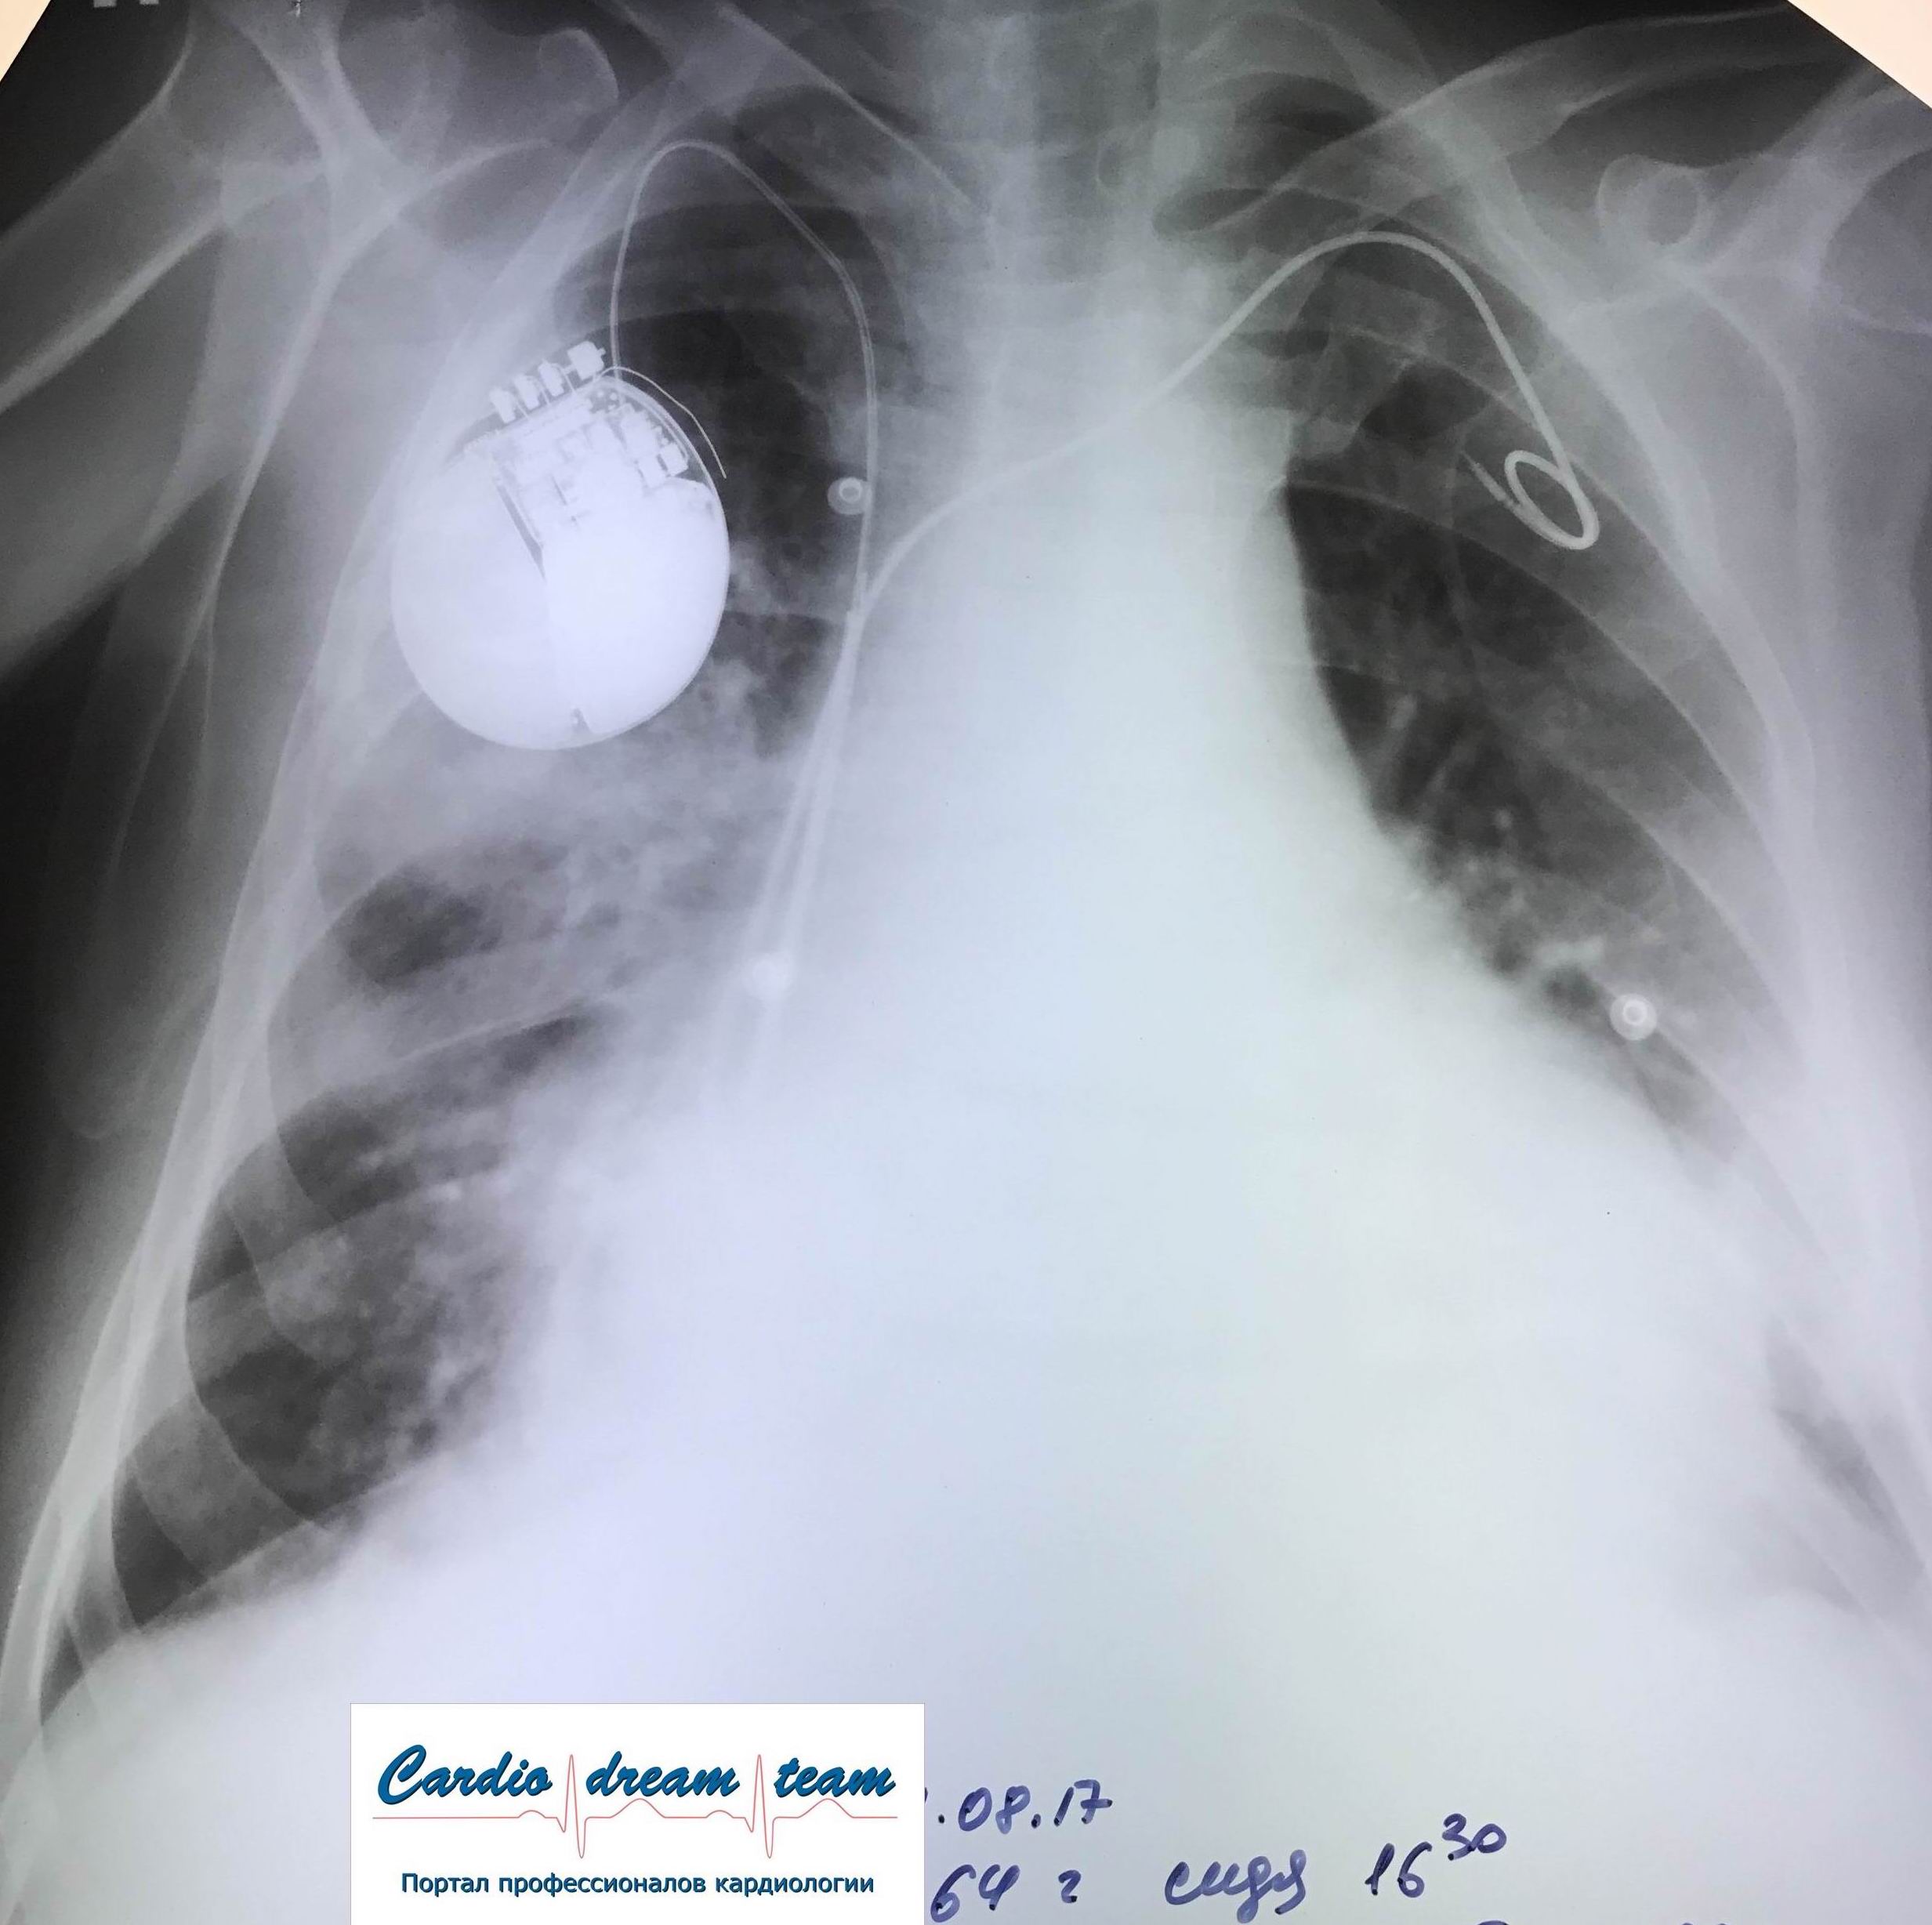

Гидроторакс. До и после пункции и лечения диуретиками.

Обсуждалось в Госпитале Ослабленных Сердец